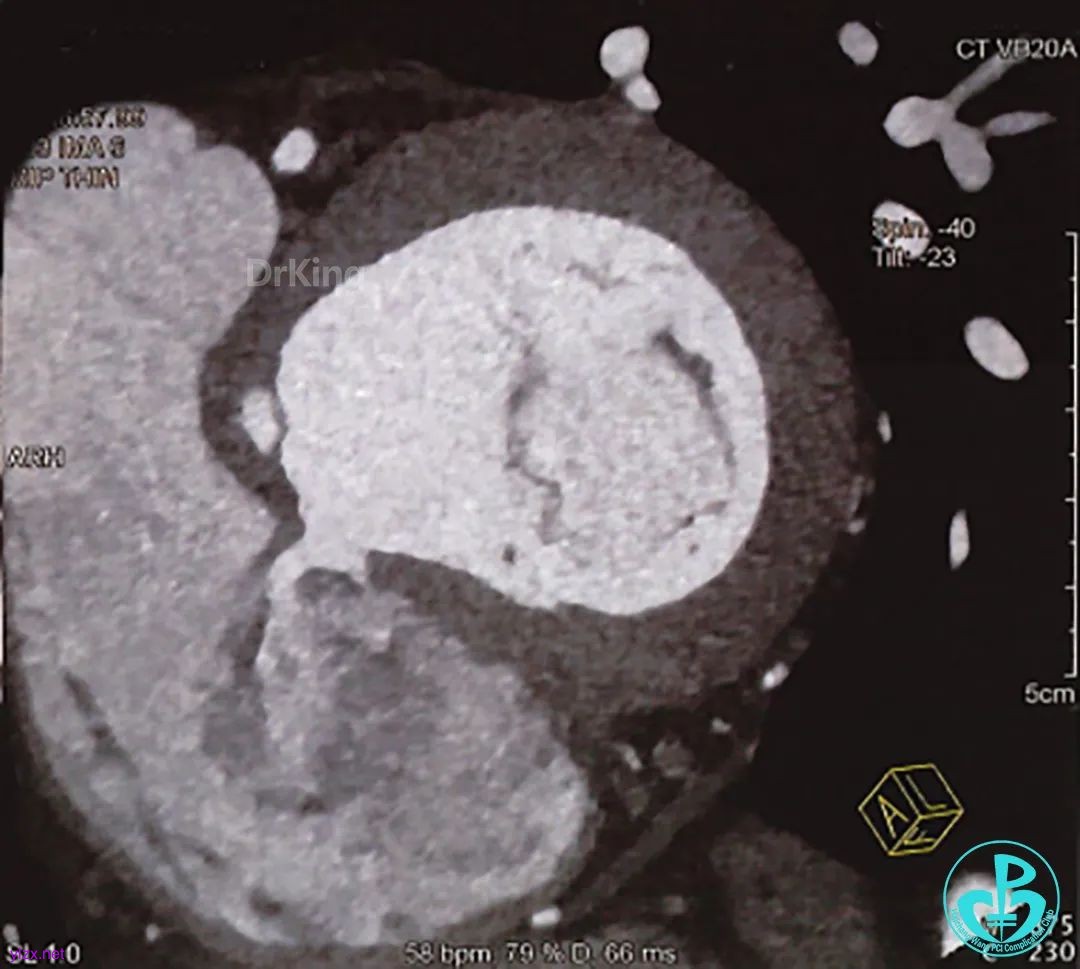

术前CT全方位判断室缺位置、形态及大小: